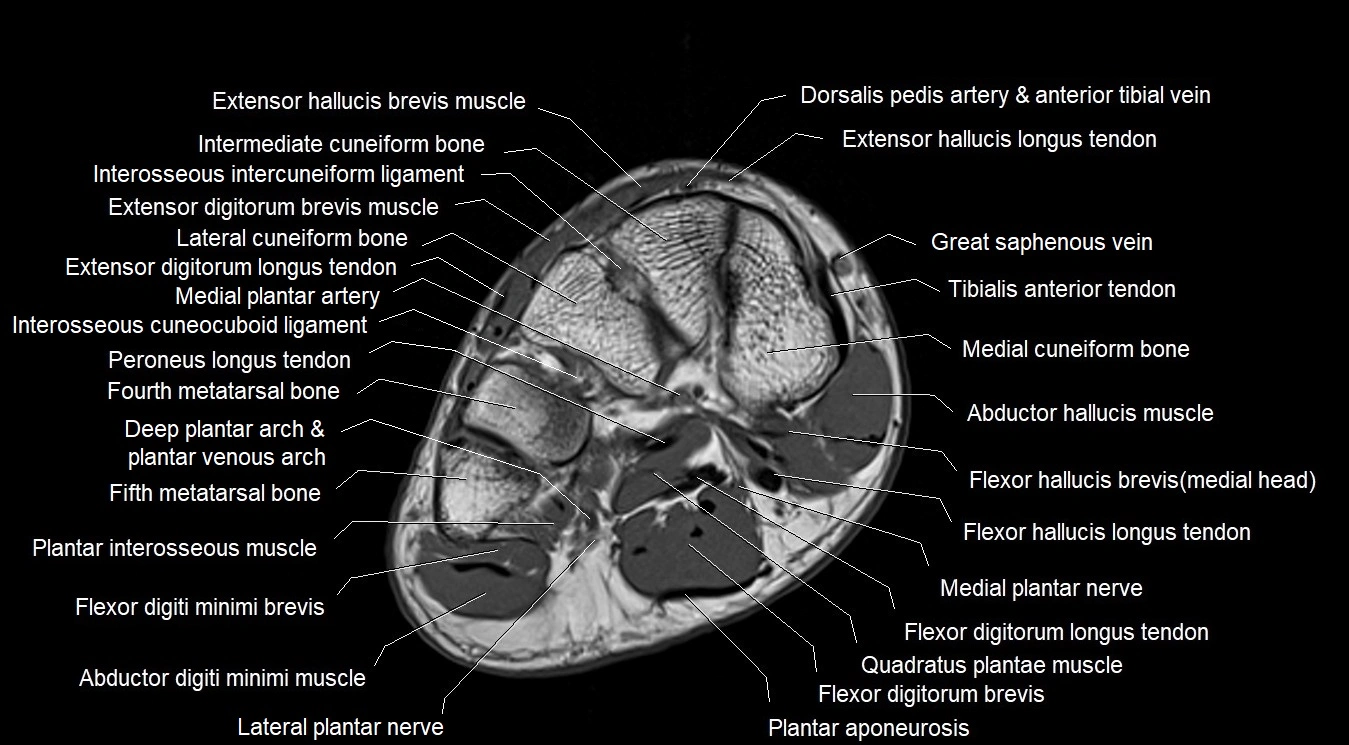

MRI image